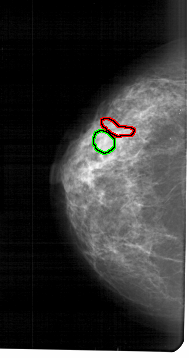

A_1470_1.RIGHT_MLO

FILE: A_1470_1.LEFT_MLO.OVERLAY

TOTAL_ABNORMALITIES 2

ABNORMALITY 1

LESION_TYPE MASS SHAPE LOBULATED MARGINS CIRCUMSCRIBED

ASSESSMENT 3

SUBTLETY 3

PATHOLOGY BENIGN

TOTAL_OUTLINES 1

BOUNDARY

ABNORMALITY 2

LESION_TYPE CALCIFICATION TYPE PLEOMORPHIC DISTRIBUTION CLUSTERED

ASSESSMENT 4

SUBTLETY 1

PATHOLOGY MALIGNANT